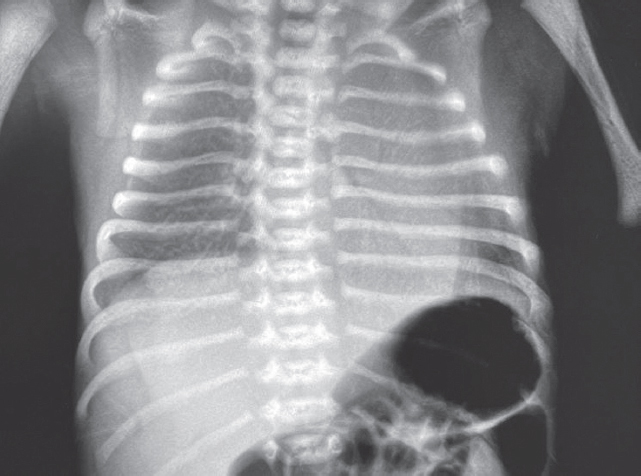

Учитывая наличие правостороннего пневмоторакса и рентгенологических признаков тяжелого РДС с преимущественным поражением левого легкого, принято решение о монобронхиальном введении порактанта альфа. На фоне проведения ВЧО ИВЛ, через эндотрахеальную трубку в левый главный бронх введен порактант альфа в дозе 100 мг/кг. Манипуляция осуществлялась под рентгенологическим контролем.

На этом фоне отмечается выраженный положительный эффект в виде увеличения SpO2 с 7–23 до 90 %, на контрольной рентгенограмме сразу после введения порактанта альфа (рис. 3) отмечается незначительное улучшение пневматизации левого легкого, сохраняется свободный воздух в правой плевральной полости.

Рис. 3. Рентгенограмма органов грудной клетки новорожденного после монобронхиального введения сурфактанта

Fig. 3. Chest X-ray of newborn after monobronchial surfactant administration